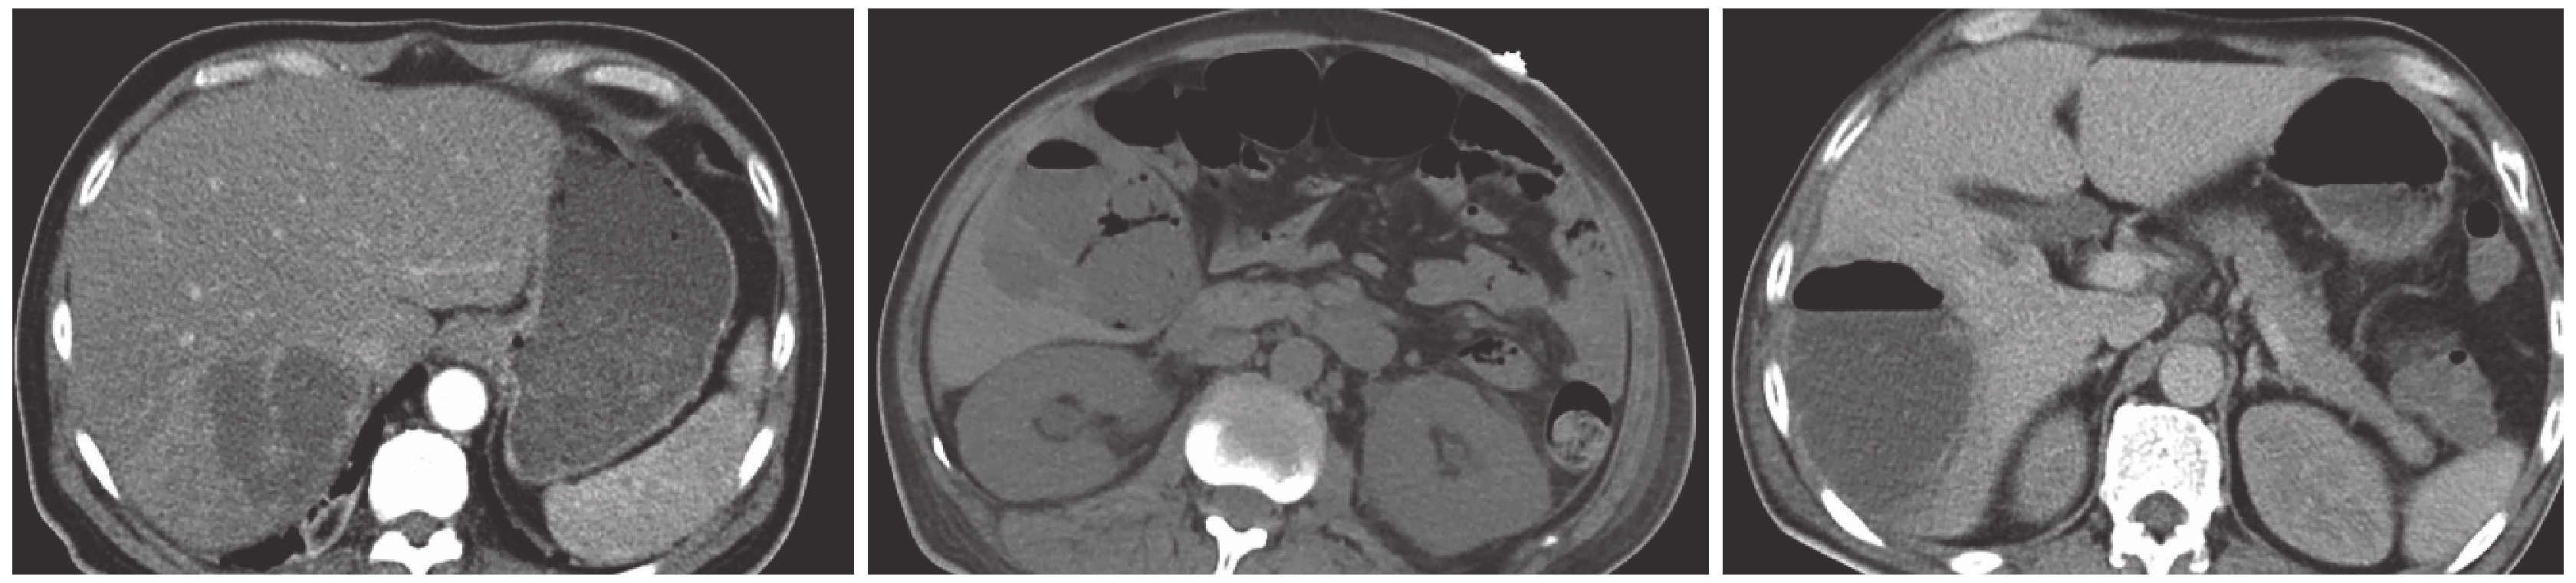

胸部 CT 檢查影像表現:結節影或伴空洞的結節影 8 例(100.0%)(結節直徑≤3 cm,并且大部分近胸膜處,圖 1a),滋養血管征 4 例(50.0%,圖 1b),近胸膜處楔形浸潤影 5 例(62.5%,圖 1c),反暈征 1 例(圖 1d),斑片狀浸潤影 3 例(37.5%,圖 1e),胸腔積液 7 例(87.5%,均為雙側積液),肺外浸潤影 1 例(12.5%,圖 1f),無淋巴結腫大影。8 例患者均經肝臟 CT 檢查(圖 2),2 例增強 CT。肝膿腫直徑 1.9~10.2 cm,平均(5.9±2.4)cm;伴空洞影 4 例。其中單發肝膿腫 5 例,多發肝膿腫 3 例。病變部位:肝右葉 7 例,肝下極 1 例。

SPE-KPLA 患者胸部 CT 特征性影像為:(1)近胸膜處多發結節影(或伴空洞)(本組患者全部出現);(2)近胸膜處楔形浸潤影;(3)滋養血管征。本組患者與 Yang 等[10]報道的 9 例患者均出現兩肺外周邊界模糊圓形結節影相一致。另外,胸部 CT 還可出現斑片狀浸潤影(嚴重病例斑片浸潤與結節影相互融合成大片實變影)、雙側胸腔積液、暈征和反暈征、肺外浸潤影(如眼內炎)。本組中 1 例患者頭顱 CT 提示左眼瞼軟組織腫脹,Yang 等[10]報道的 9 例患者中 3 例出現眼內炎。肝臟 CT 檢查示肝膿腫往往多伴空洞影(本組占 50%),Lee 等[16]曾提及產氣肝膿腫死亡率較高。單發肝膿腫多見(62.5%),發生部位以肝右葉(87.5%)多見。